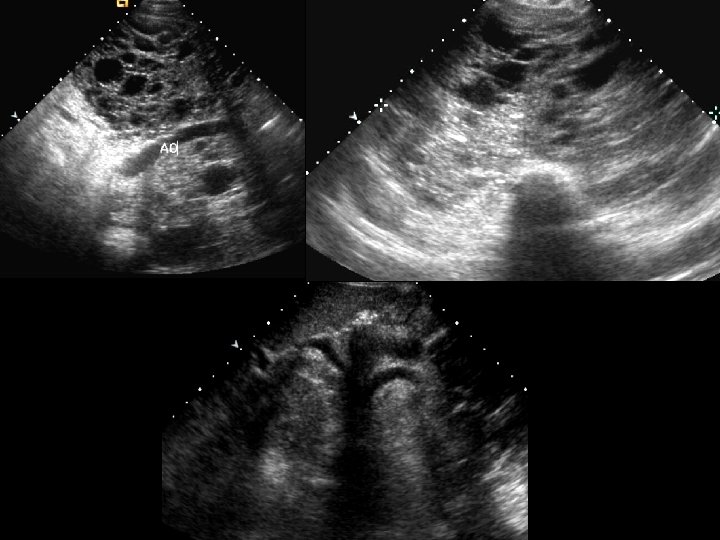

Erythroblastosis Fetalis • Findings: – anasarca, cardiomegaly, ascites, effusion • a. k. a. Immune hydrops fetalis or hemolytic disease of the newborn • maternal Ab enter fetal circulation and destroy RBCs causing anemia • infant is edematous, icteric, and hypotonic • ddx: – non-immune hyrdops